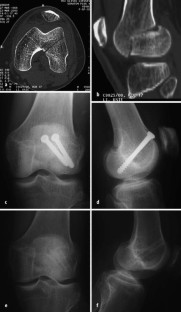

Abb. 1

Abb. 2

Abb. 3

Abb. 4